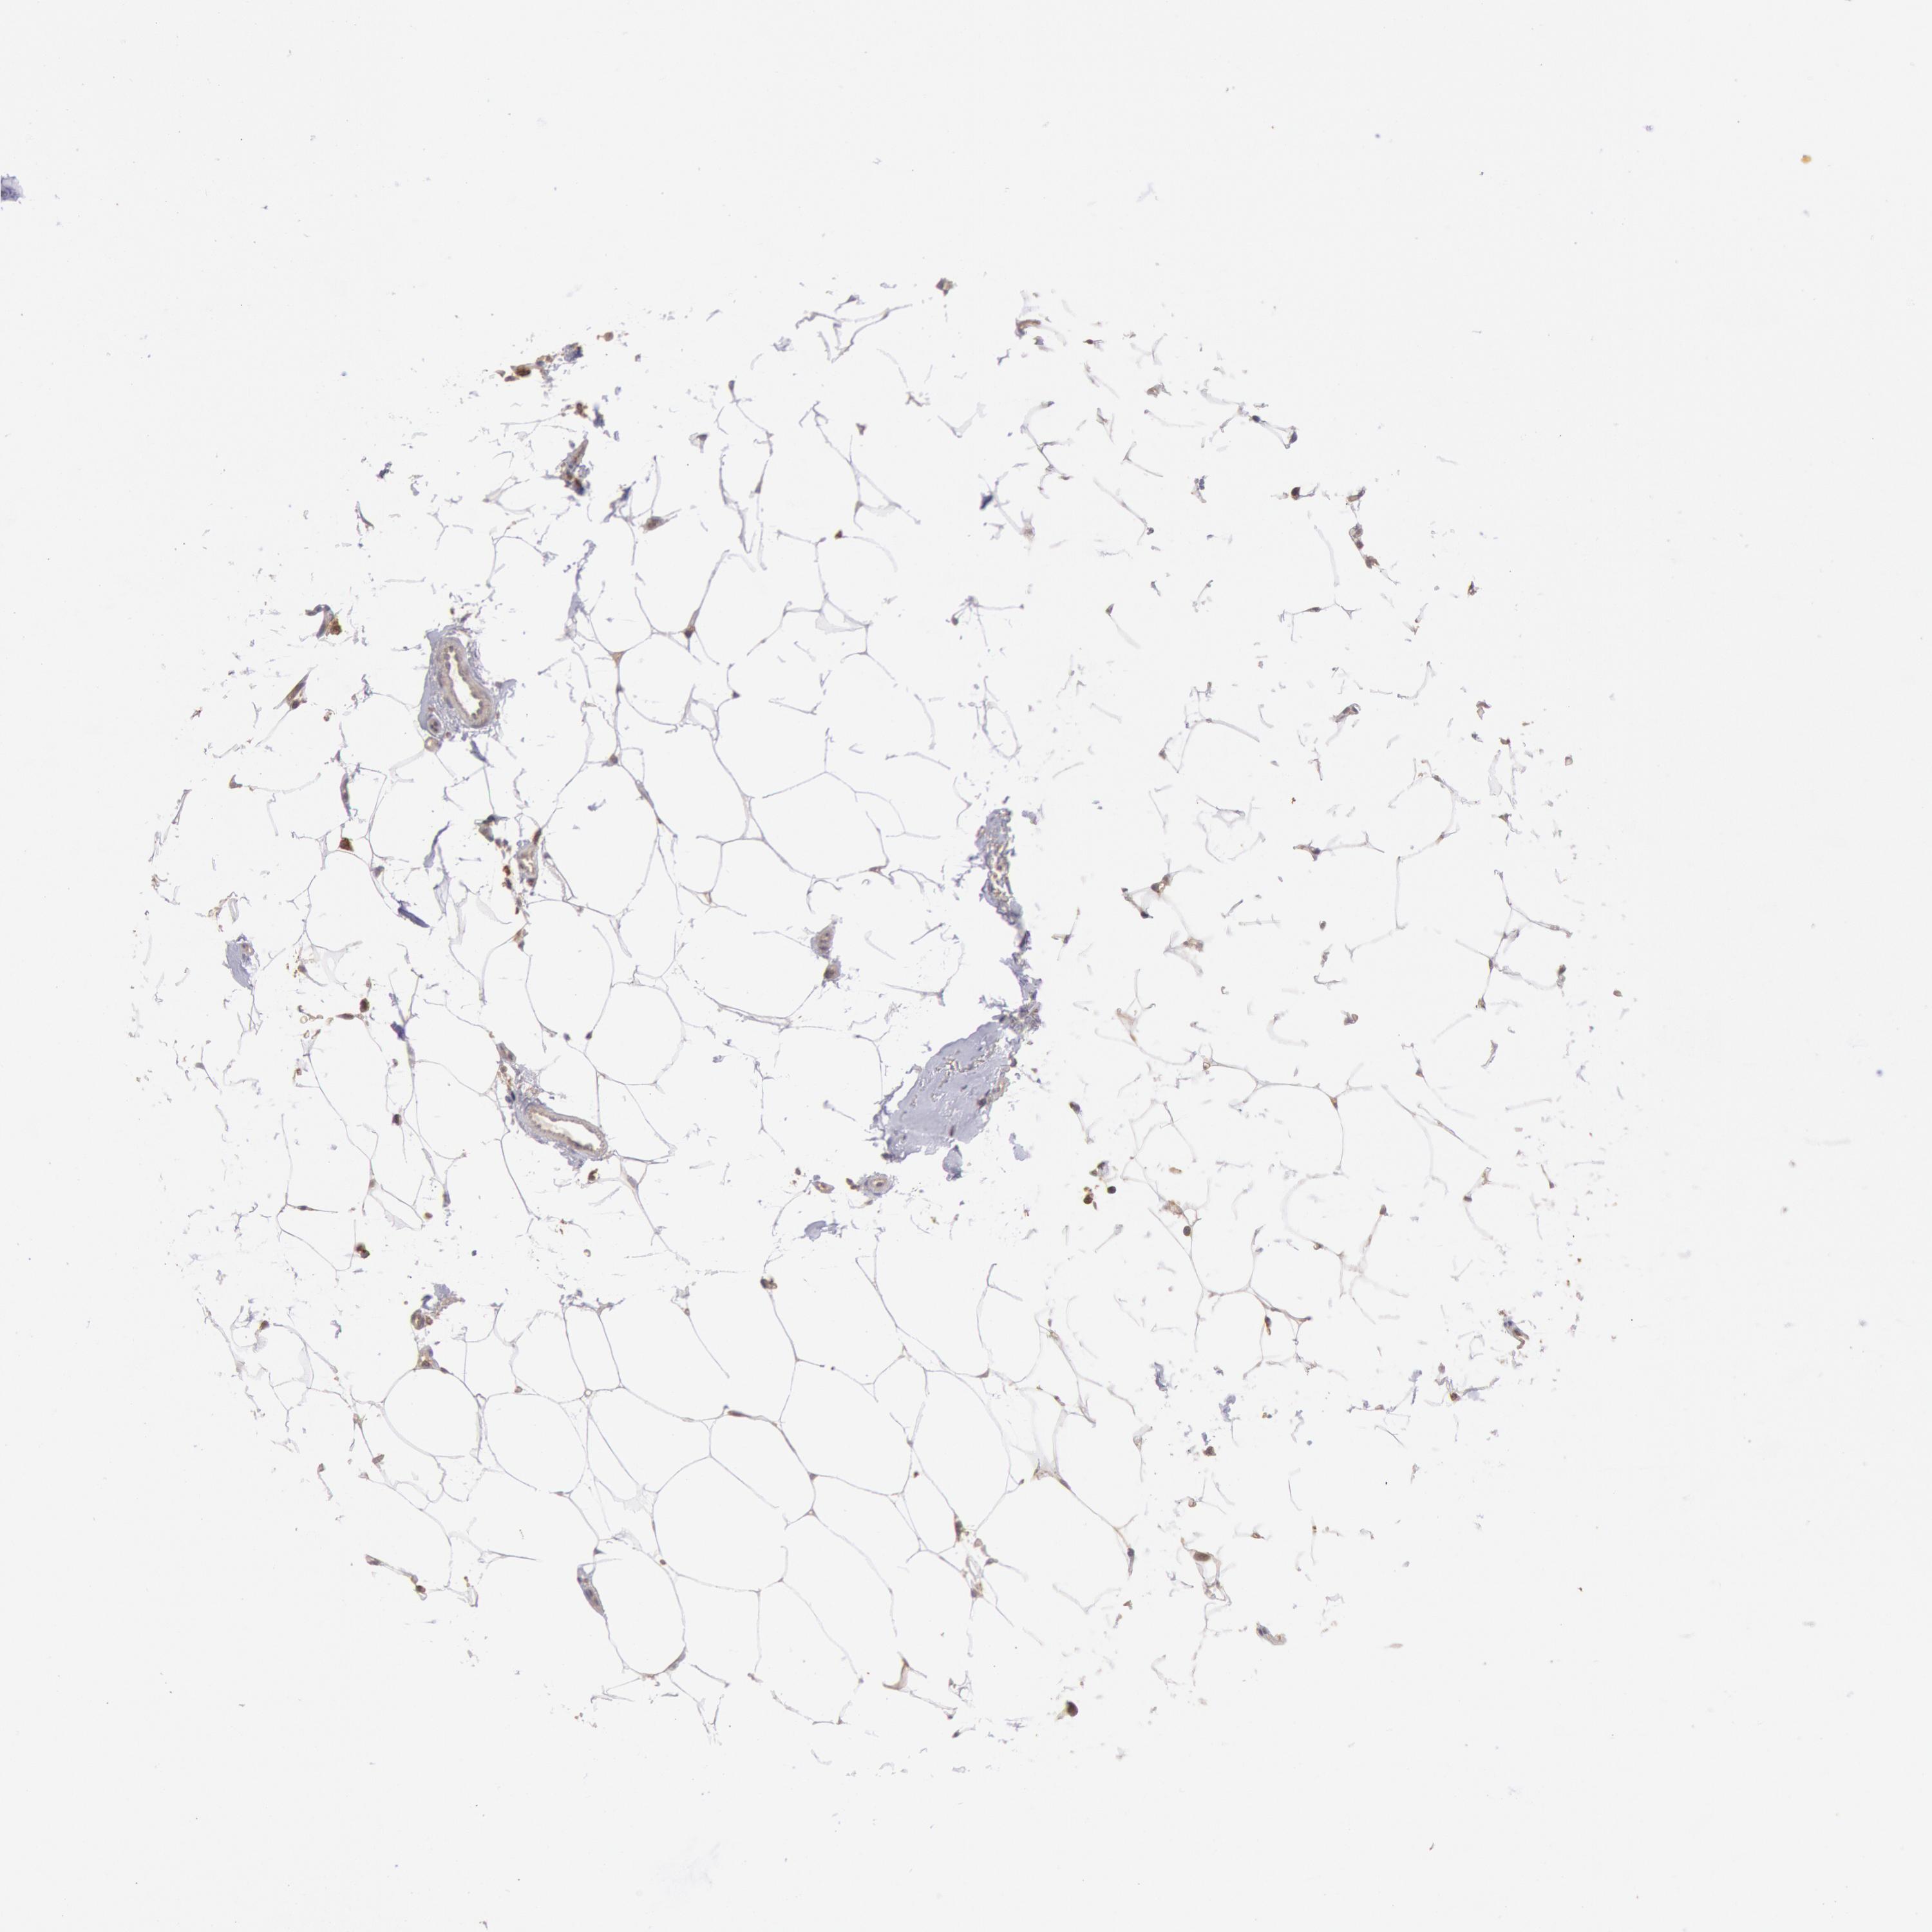

CANCER BREAST CANCER Show tissue menu

BRCA TCGA BRCA VALIDATION PROTEIN EXPRESSION